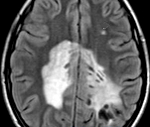

Демиелинизирующие заболевания мозга: МРТ изображения